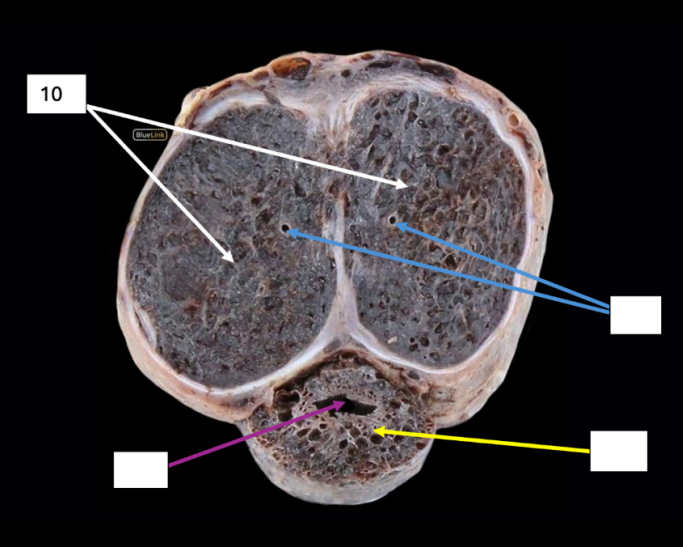

Testis

Identify

Side Question:

This is surrounded by which structure?

This is divided into lobules by which structure?

Blood Supply?

Venous Drainage?

Nerve Supply?

Lymph Drainage?